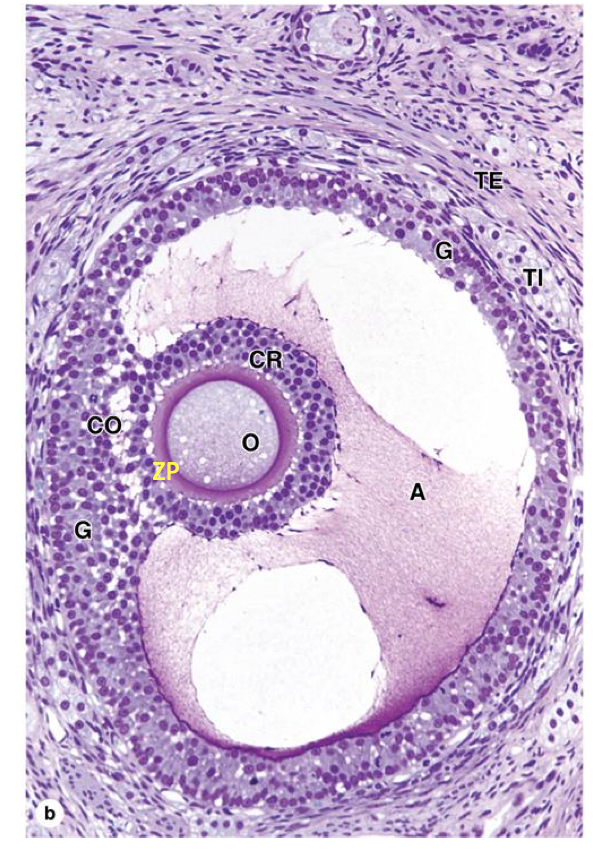

graffian follicle ready to ovulate

corpus luteum

a= theca lutein cells b= granulosa lutein cells